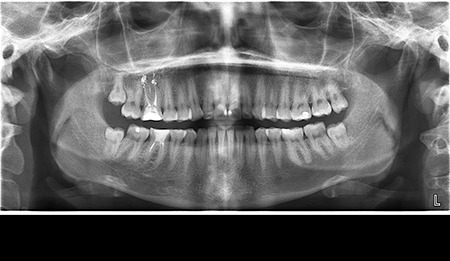

- Цифрова панорамна рентгенографія (ортопантомограма) – дає цілісне зображення всієї щелепно-лицевої системи.

Що ви уявляєте, коли лікар говорить про ортопантомограму? Насправді, це знімок усієї зубощелепної системи, який охоплює обидві щелепи, гайморові пазухи та скронево-нижньощелепні суглоби. Таке оглядове фото дозволяє стоматологу отримати загальне уявлення про стан зубів, кісткових структур та навколишніх тканин.

Ортопантомограма Полтава є незамінною при первинній діагностиці, коли потрібно оцінити загальний стан ротової порожнини. Її призначають у наступних випадках:

- для виявлення прихованих каріозних уражень;

- для оцінки стану пародонту (ясен і кістки);

- перед ортодонтичним лікуванням;

- перед видаленням зубів мудрості;

- для моніторингу росту та прорізування зубів у дітей.

Цифрова панорама Полтава успішно використовується для первинної діагностики в момент першого звернення до лікаря, бо дозволяє виявити всі патологічні процеси в зубах, кістці, навколощелепних тканинах. Завдяки їй лікар не припуститься помилок під час планування й виконання складних ортопедичних робіт.

Діагностика зубів Полтава із застосуванням ортопантомограми має ряд переваг:

- швидке та безболісне обстеження (триває всього кілька хвилин);

- мінімальна доза опромінення – робить процедуру безпечною навіть для дітей;

- загальний огляд усієї порожнини рота на одному знімку – максимальна інформативність для стоматолога;

- можливість зберігання знімків у цифровому форматі для подальшого порівняння та динаміки лікування.